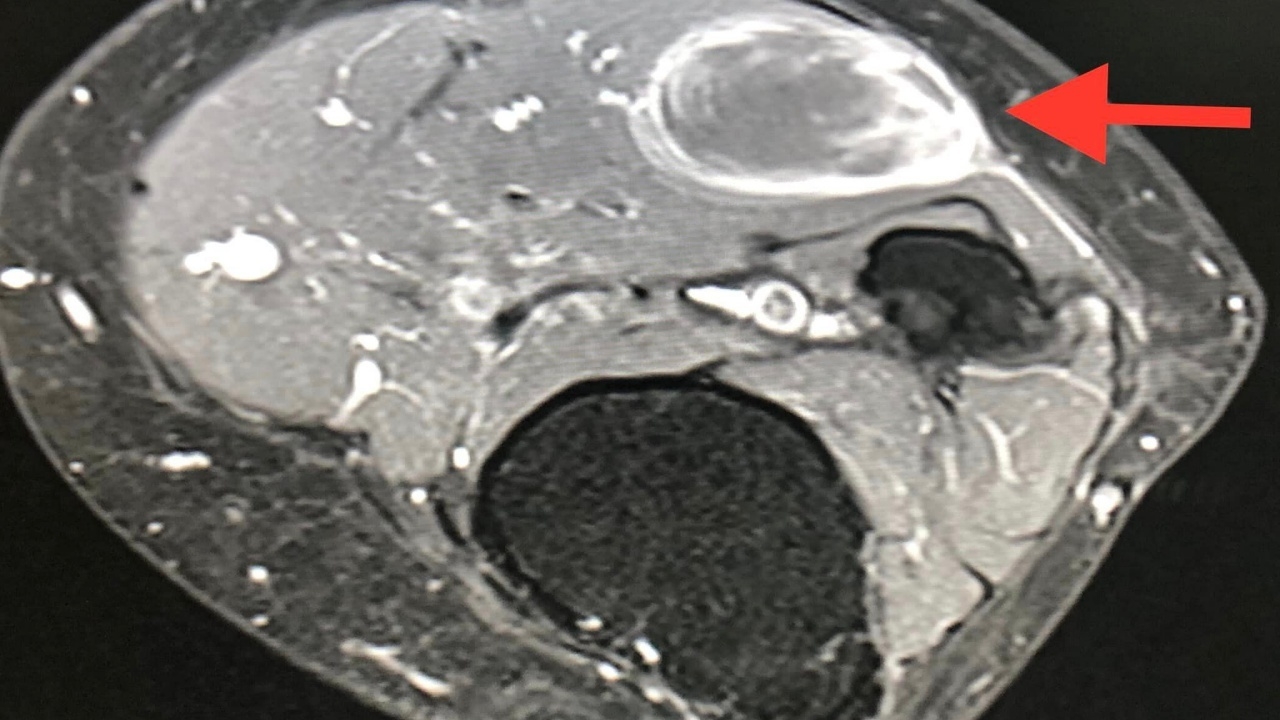

ผู้ป่วยหญิงอายุ 61 ปี ปกติแข็งแรงดี คลำได้ก้อนที่ขาใต้หัวเข่าข้างขวา ด้านนอกขนาด 5 เซนติเมตร (ดูรูป) ก้อนนูนแข็ง ขยับก้อนได้ ค่อยๆ โตขึ้น ไม่เจ็บ เดือนมีนาคม 2565 ทำ MRI ตรวจคลื่นแม่เหล็กไฟฟ้า พบก้อนขนาด 3.5 x 2.2 x 5.1 เซนติเมตร อยู่ชั้นใต้ผิวหนังติดกับกล้ามเนื้อของขา สงสัยมะเร็งเนื้อเยื่ออ่อน (soft tissue sarcoma) (ดูรูป)

ผ่าตัดกว้างเอาก้อนเนื้อที่ขาออก เมื่อเดือนเมษายน 2565 ส่งตรวจพยาธิวิทยาเป็น Myxofibrosarcoma มะเร็งของเนื้อเยื่อเกี่ยวพัน ขนาด 4.8 x 4.2 x 6 เซนติเมตร เกรดสูงระดับ 3 ไม่พบมะเร็งที่ขอบรอบๆ ก้อนเนื้อที่ตัดออก แสดงว่าแพทย์ผ่าตัดเอาเนื้องอกออกได้ทั้งหมด